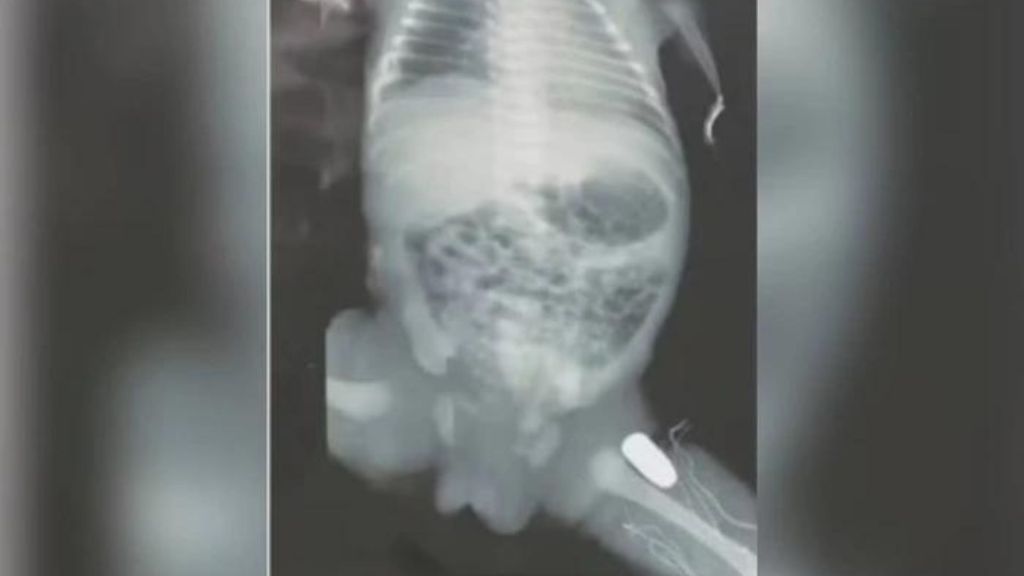

PROJÉTIL FICA ALOJADO EM PERNA DE BEBÊ AINDA NA BARRIGA DA MÃE EM IMPERATRIZ

🚨 Uma grávida foi baleada no Maranhão, e o projétil ficou alojado na perna do bebê. O caso aconteceu em Imperatriz. Quem traz os detalhes é o repórter Marvio Araújo. Não perca! 📺 #Notícia #Imperatriz #Maranhão #Segurança